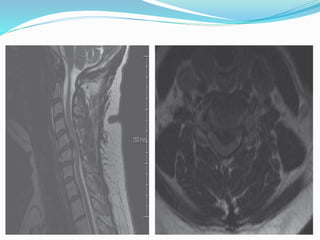

 MRI cervical spine

Investigations  Specific : Xray cervical spine (AP XTSX CC)  MRI cervical spine  CT scan cervical spine  Routine :  CBC ,SUCE , PT/APTT/INR . Hep b & c . CXR  Relevant :